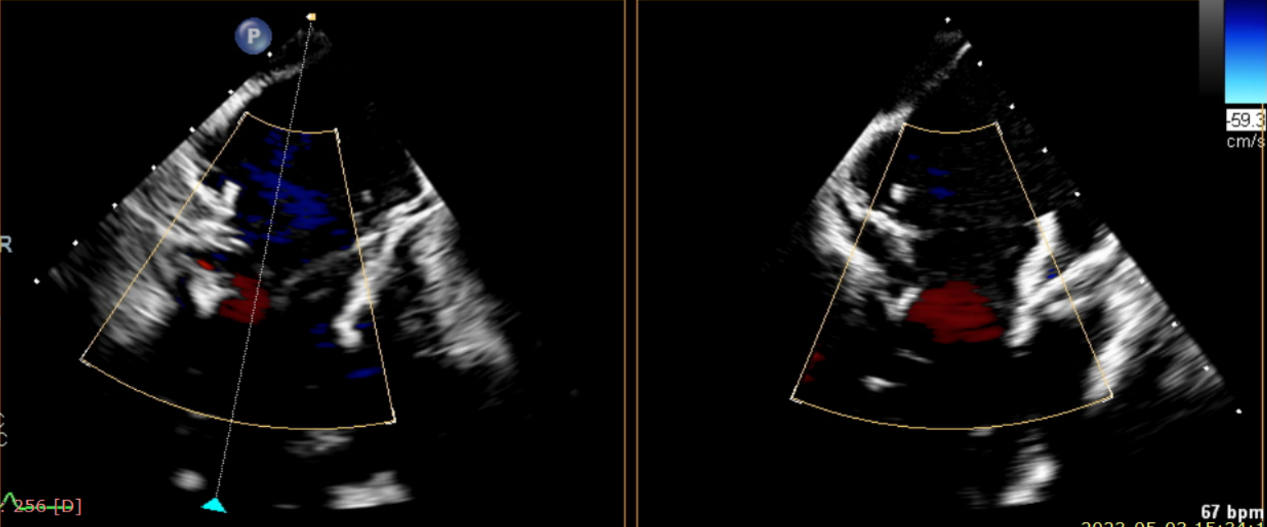

術前超聲提示大量三尖瓣反流

術后超聲提示無瓣周漏

術后超聲提示僅殘余輕微瓣周漏